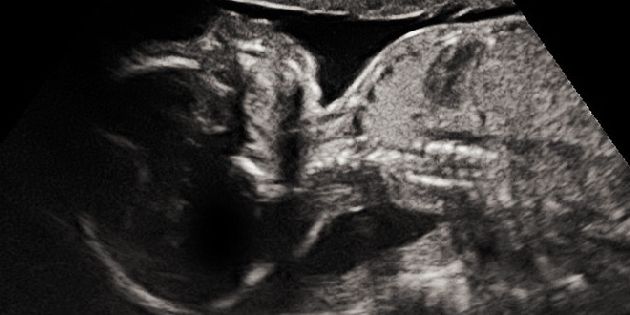

Narození dítěte se závažnou vrozenou vývojovou vadou patří mezi nejzávažnější rodinné tragédie. P...